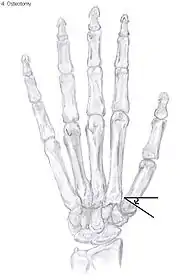

Metacarpal osteotomy

The aim of this procedure is to change the pressure distribution on the CMC1 joint, so it can function without further damaging the joint. That is why a successful osteotomy requires a CMC1 joint of reasonable condition. Therefore, the metacarpal osteotomy should be limited to patients with a stage I-II CMC OA.[24]

An osteotomy is a surgical procedure wherein bone fragments are modified by cutting the bone.

During this procedure an abduction osteotomy of the proximal end of the first metacarpal bone is performed. An incision is made over the radial border of the first metacarpal bone. A wedged shape bone fragment is removed, causing the distal part of the metacarpal bone to tilt towards its desired position.[36] Postoperative, the thumb of the patient is immobilized using a thumb-cast.

Possible complications are non-union of the bone, persistent pain related to unrecognized CMC or pantrapezial disease and radial sensory nerve injury.[24]